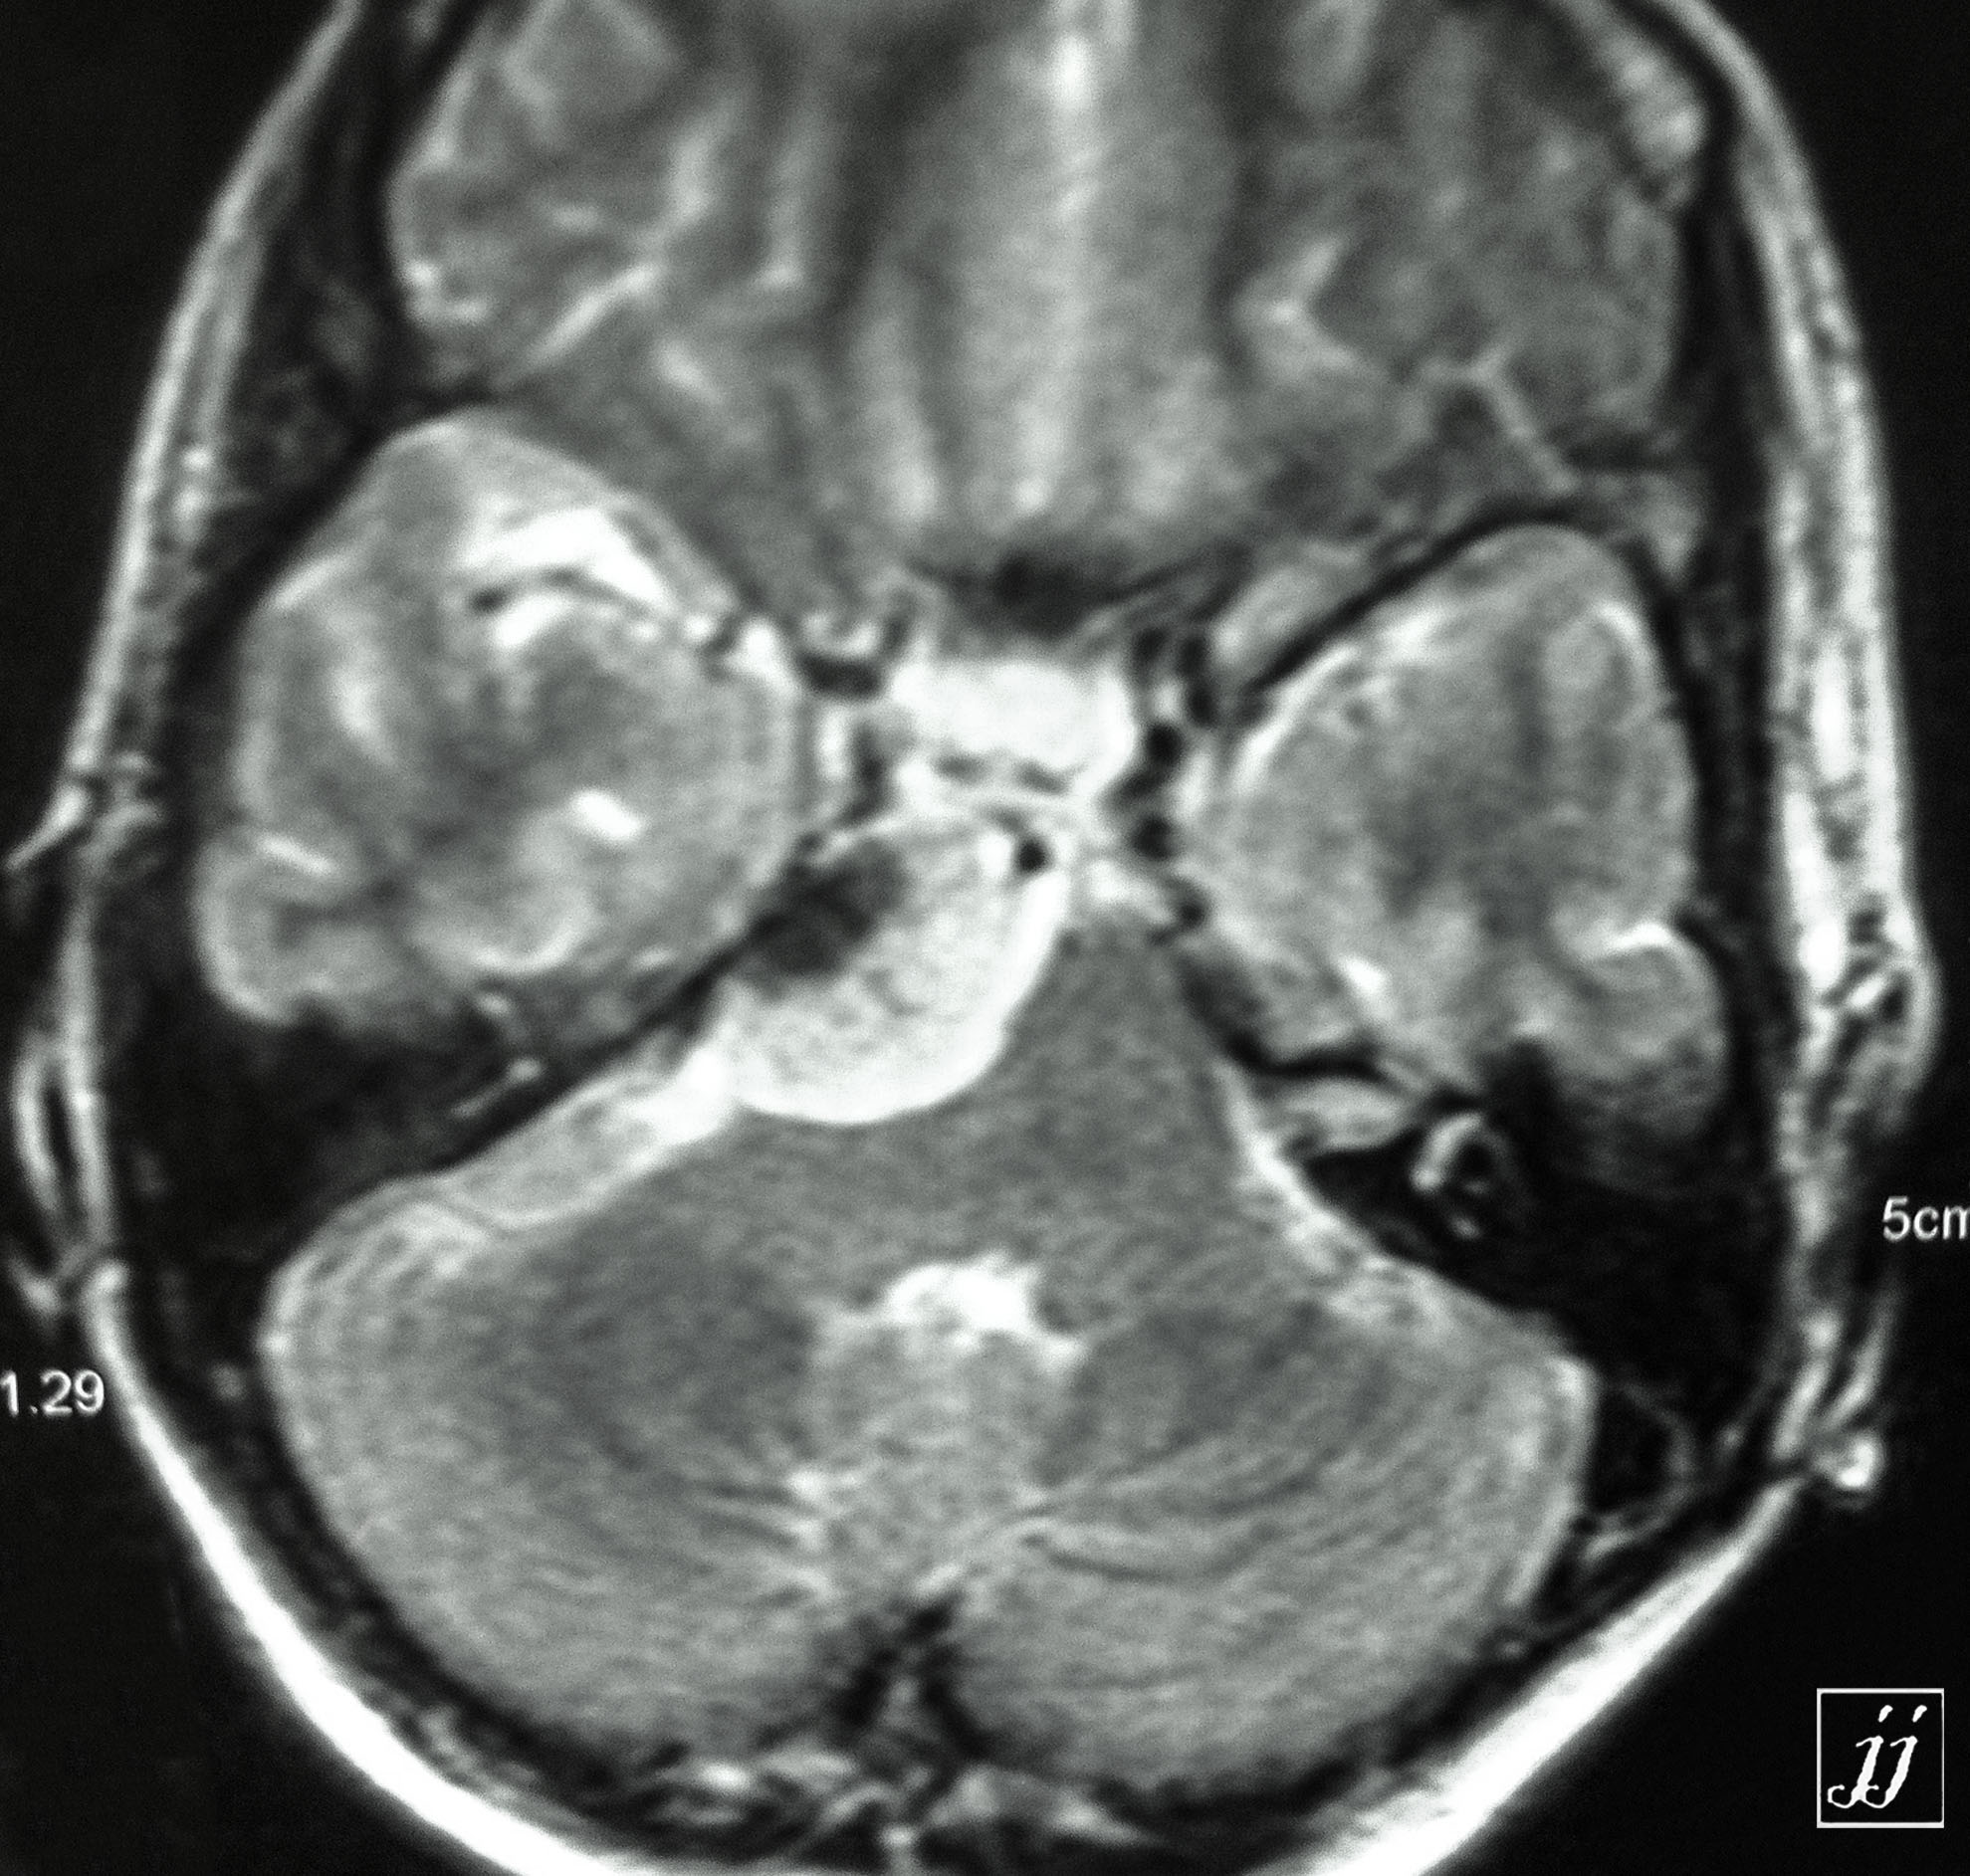

Brain- cystic vestibular schwannoma vs hemangioblastoma (8)